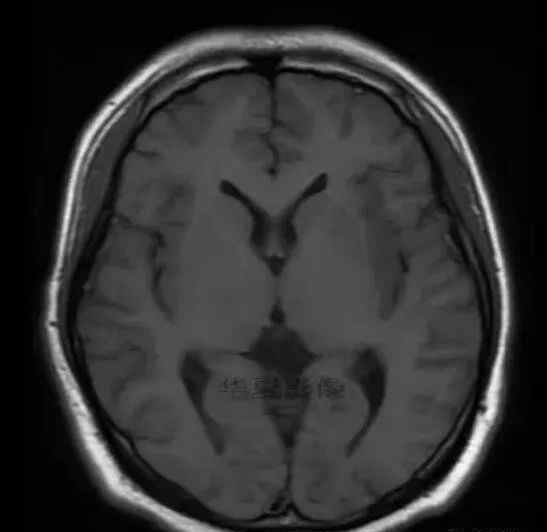

男,25岁,6天前意外感冒,现在发烧。他的体温超过39.0℃,他的呕吐物不是喷射状的。他的呕吐物是胃里的东西。

1.左侧颞叶、海马和岛叶T1WI信号低,T2WI信号高

2.病变没有明显的边界

3.占用效果不明显

4.豆状核不受影响